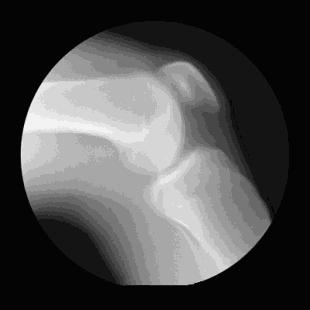

「关节软骨」是一个非常重要的"部件",它主要便于骨与骨之间的运动,增加关节的活动性。

人年轻时,软骨在磨损的同时,软骨也能"自我修复"(软骨细胞能新生)。但随着人年纪的增长,软骨细胞的新生能力严重下降,软骨磨损又多,退变就出现了。

(可以试想下,当软骨磨损严重时,骨头和骨头之间的"硬摩擦"到底有多痛)